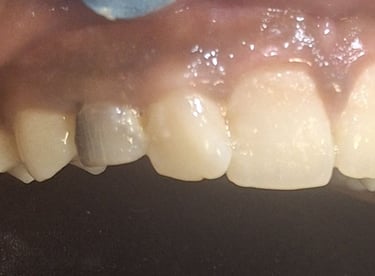

All images shown here represent real clinical cases of teeth extractions done at our dental clinic with patient consent.

Illustrative images and similar real clinical cases requiring tooth extraction